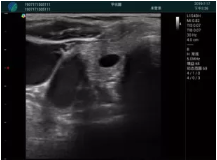

甲狀腺囊性結(jié)節(jié),囊壁鈣化,透聲好

甲狀腺囊性占位

M20查看:囊內(nèi)回聲均勻,邊界清晰,囊壁光滑

M20引導(dǎo)抽吸術(shù)后囊腫消失,原區(qū)域空腔形成,脂肪層與腺體層架構(gòu)發(fā)生改變